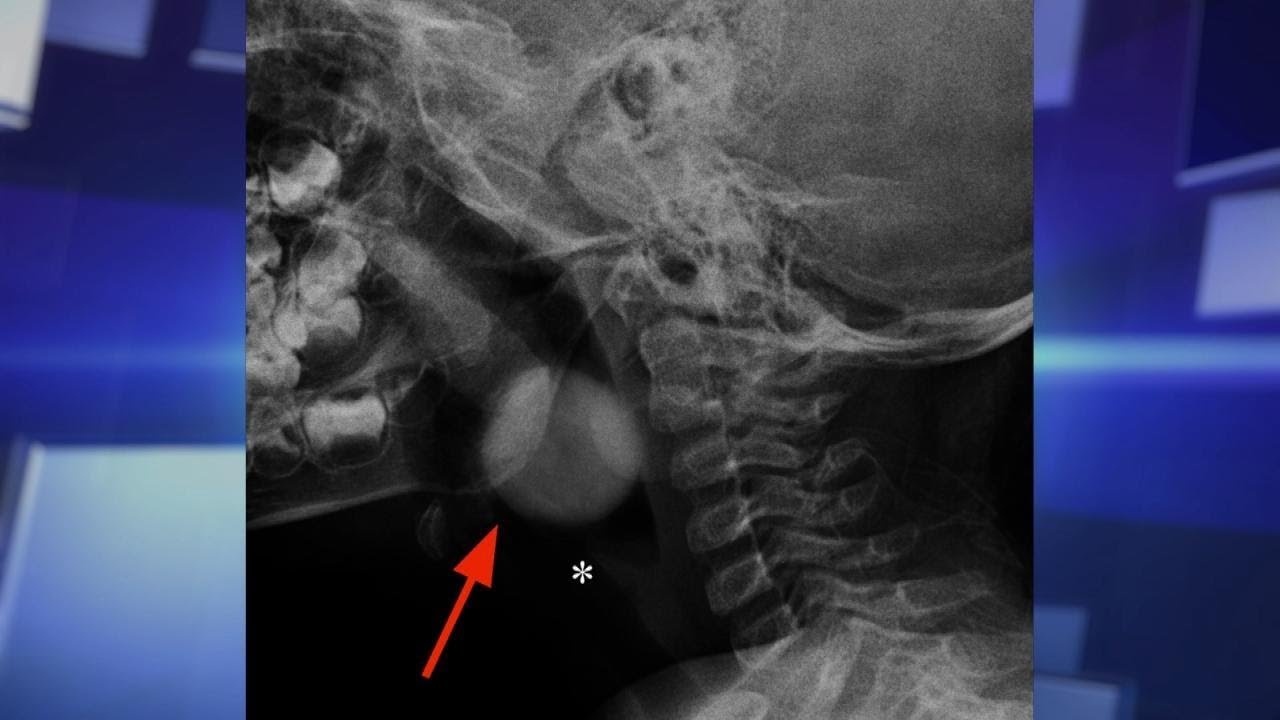

Children under 4 years old don’t have the ability to thoroughly chew food and it can easily get caught in their small windpipes. The Doctors share some tips to keep your loved ones safe.